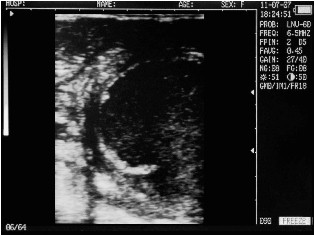

Ultrasound images of cows reproductive system, generated by a scanner Sonovet with rectal linear transducer.

Uterine horn heifers